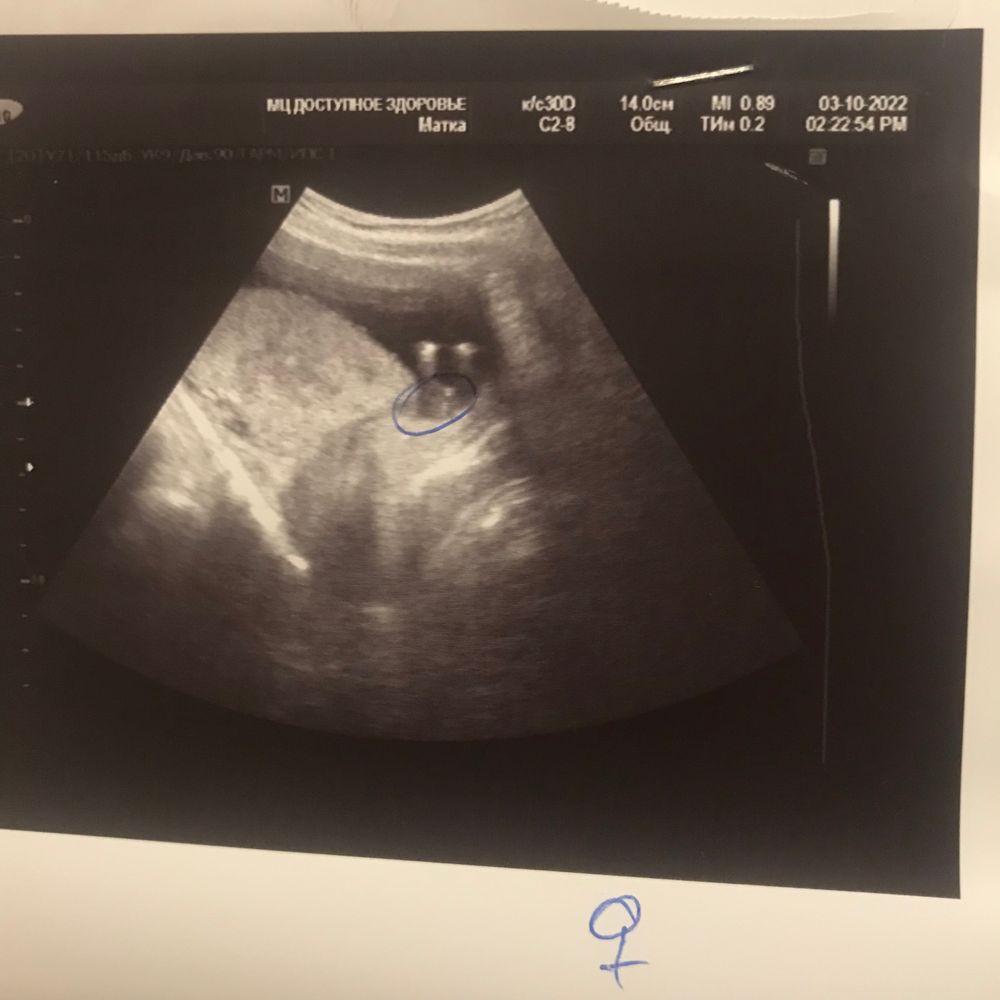

Узи пол ребёнка

На этом сроке смотрят по наклону бугорка, а не между ног 😅

Насколько я знаю, раньше 18 недель безполезно смотреть пол. Странный УЗИст... При вероятности 50/50 мог бы просто устно сказать и посмеяться, а не в заключении писать

Ну я думаю на таком сроке ничего нельзя увидеть, на 14-15 неделе вроде бы только заканчивается формирование. Я в 16 недель ходила в платную и там мне сказали мальчик, после в 20 недель все подтвердилось))

С вероятностью 50% - это мужик)

N N, на таком сроке только предполагают. И все совпадения случайны😁 Недели через 4 уже будет видно)

Пол малыша в 12,4 недели на скрининге Когда узнали пол малыша